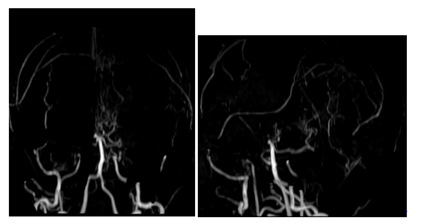

This is a 27year-old woman who has been known to have had sickle cell anemia since childhood, and who brutally presented a picture of meningeal haemorrhage caused by severe headache, vomiting. The clinical examination finds a patient subbérile subfebrile with a stiff neck. An MRI performed urgently in the three planes of space in weighted sequences T1, T2 FLAIR and angio-RM arterial. It reveals intra-ventricular haemorrhage as well as fine serpiginous vascular structures in the sylvian valleys and peri-mesencephalic. MRA shows the absence of the supraclinoid segments of the internal carotids with development of a fine cortical anastomotic network and at the Willis polygon Figure 1 & 2.

Figure 1 Cerebral angioplasty MRI performed urgently: in the 3 planes of space in T1, T2, FLAIR and angio-RM arterial: hyposignal T2 and hypersignal T1, intraventricular FLAIR. Demonstration of multiple serpiginous structures in hyposignal T2 and FLAIR sitting at the level of the permeesencephalic tank and the sylvian valleys.

Figure 2 Arterial Angio-MRI in flight time: absence of visualization of the supraclinoid segments of the internal carotids as well as the proximal portions of the anterior and middle cerebral. A cortical anastomotic network is located at the base and visualization of the distal segments of the cerebral arteries where the flow is slowed down.